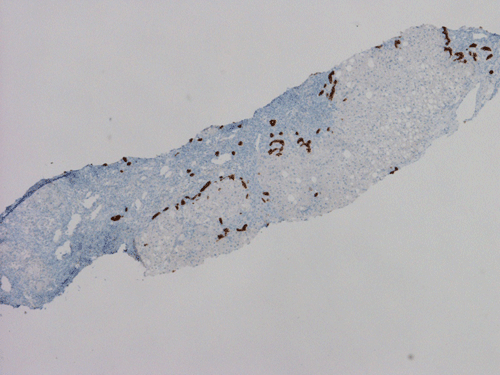

Pathology of the Case: At low magnification, a few small nodules (arrow in Panel A) can be seen with the hematoxylin and eosin stained section. On medium magnification, these nodules correspond to sharply defined granuloma without necrosis. These granuloma are not associated with a high density of lymphocytes in the surrounding liver parenchyma (Panel B and C). Multinucleated giant cells (arrow in Panel C, magnified in Panel D). On reticulin stain, there are reticulin fibers that extends into the granuloma (Panel E). Trichrome stain demonstrated bridging fibrosis (Panel F). The granuloma are well defined and some of them are surrounded by fibrous tissue (Panel G). Immunohistochemistry demonstrated preservation of bile ductules as well as proliferation of ductules (Panle H). No residual ductules are noted in the granuloma as revealed by immunohistochemistry for CK7 (Panel I). Neither acid fast bacilli or fungal organisms are identified by acid fast stain and Gomori's methenamine silver (GMS) stain.

Histopathologic features of sarcoidosis include scattered granulomas in the liver, which may tend to be portal or periportal. Multinucleated giant cells, epithelioid cells, and a variable but usually minimal inflammatory cellular response is present. The granulomas, like in sarcoidosis occuring in other organ systems, tend to be well-demarcated or "clear cut", several granulomas are often comparable in size, and necrosis is not typically present. Asteroid bodies, intracellular vacuolated structures resembling a sea anemone, may be found within the giant cells. Large basophilic, round to roughly oval, and concentrically laminated, Schaumann bodies may be evident in the sarcoid granuloma. None of these inclusions are pathognomonic feature of sarcoidosis, however, do suggest this diagnosis. Ductopenia, cholestasis and features of chronic cholestasis resembling PBC have been described in the cases of sarcoidosis. Severe fibrosis and cirrhosis in conjunction with portal hypertension may be present in sarcoidosis. End stage liver disease in sarcoidosis has been successfully treated by orthotopic liver transplant and recurrent disease has been reported in one such case. Reticulin fibers has a tendency to extend into the granulomas as illustrated in this case.